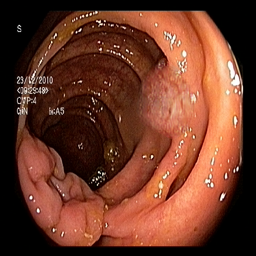

(a) Refer to caption Refer to caption Refer to caption Refer to caption Refer to caption Refer to caption

(b) Refer to caption Refer to caption Refer to caption Refer to caption Refer to caption Refer to caption

(c) Refer to caption Refer to caption Refer to caption Refer to caption Refer to caption Refer to caption

(d) Refer to caption Refer to caption Refer to caption Refer to caption Refer to caption Refer to caption

(e) Refer to caption Refer to caption Refer to caption Refer to caption Refer to caption Refer to caption

(f) Refer to caption Refer to caption Refer to caption Refer to caption Refer to caption Refer to caption

(g) Refer to caption Refer to caption Refer to caption Refer to caption Refer to caption Refer to caption

(h) Refer to caption Refer to caption Refer to caption Refer to caption Refer to caption Refer to caption

Figure 3: Sample data used and generated in the different steps of PolypConnect pipeline. (a) - real polyp images, (b) - manually annotated polyp masks, (c) - randomly selected colon images used as input to the final step of PolypConnect, (d) - extracted edge images of row c. (e) - extracted edge images of polyp regions of row a using the masks of row b. (f) - combined edge images of row d and f. (g) - generated polyp on the images of row c using EdgeConnect. (h) - generated samples from AOTGAN.